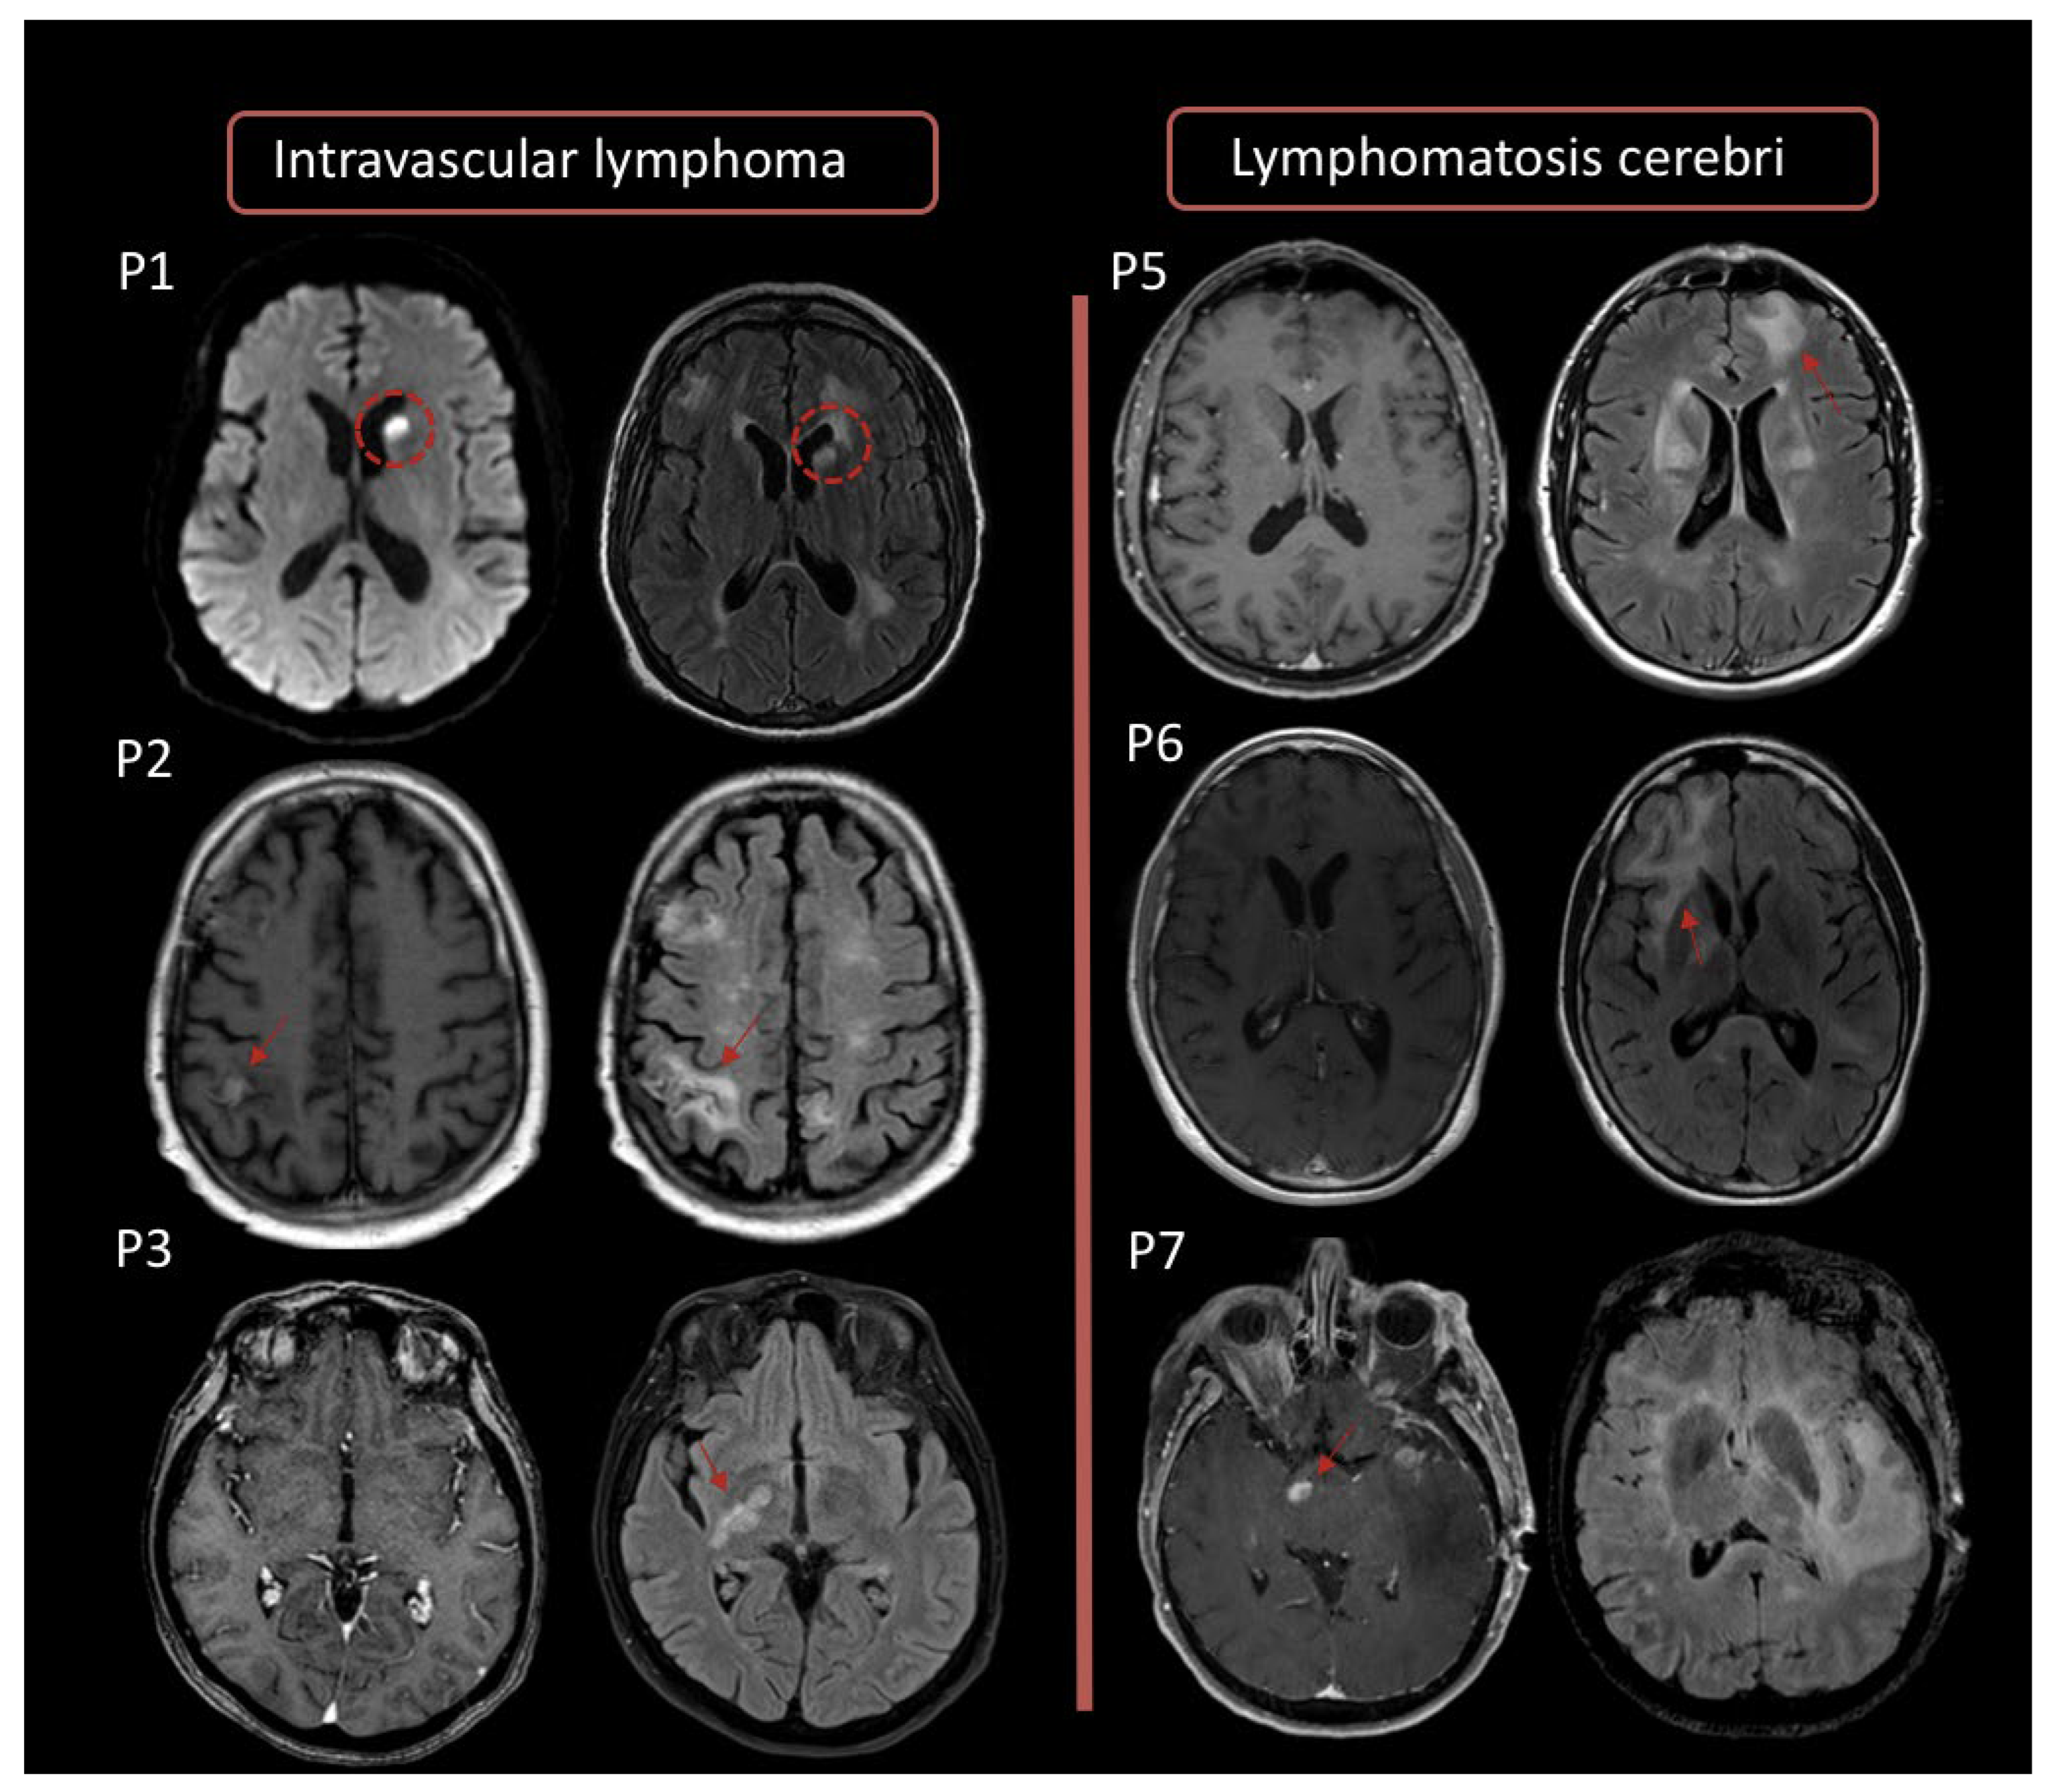

2.1. Magnetic Resonance Imaging (MRI)

2.2. 18F-FDG Positron Emission Tomography (PET)

2.2.1. Features at Diagnosis